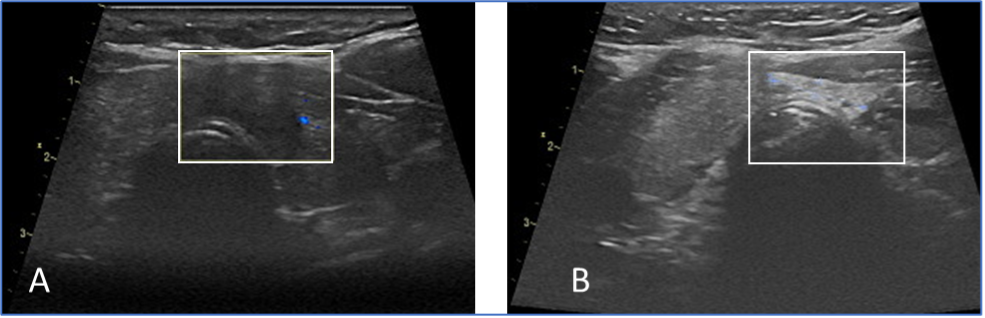

Das Schilddrüsenkarzinom (A) im weißen Rechteckt ist nach der Therapie nicht mehr nachweisbar (B). In Deutschland hat Prof. Korkusuz die meisten Ablationen von Schilddrüsenkarzinomen erfolgreich durchgeführt.